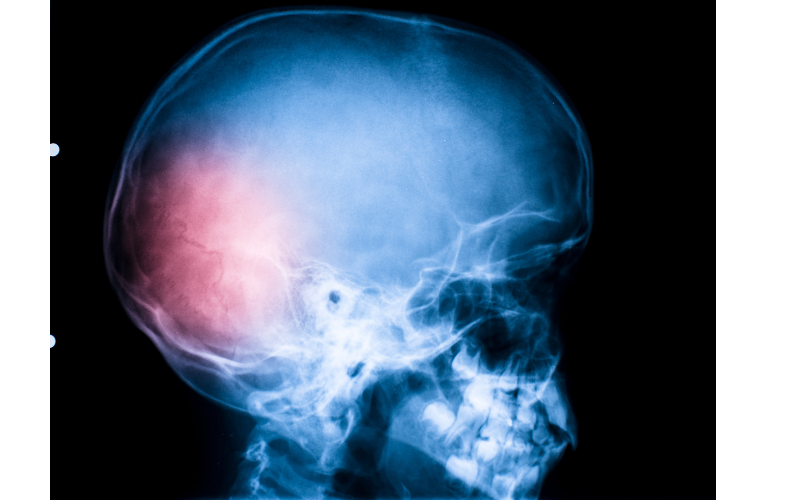

How TBI Affects the Brain—and Why Anxiety Follows

Let’s look at what actually happens inside the brain after a traumatic injury and how it ties into anxiety:

🧠 1. Damage to the Limbic System

The limbic system is your brain’s emotional center. If the injury affects parts like the amygdala (which controls fear) or the hippocampus (which processes memory), your brain can get stuck in a “threat” mode—even when nothing’s wrong.

Translation: Your body starts reacting to normal life as if it’s dangerous. Cue: anxiety, panic, hyperawareness.

🧠 2. Disruption to the Prefrontal Cortex

This part of your brain handles decision-making, impulse control, and regulating emotions. When it's damaged?

You may struggle to calm yourself down, process stress, or make sense of your own emotional waves.

🧠 3. Nervous System Dysregulation

TBI can damage the vagus nerve or interfere with how your brain communicates with your body. The result?

Your nervous system can’t find its “off switch.”

That constant fight-or-flight state isn’t in your imagination—it’s neurological.